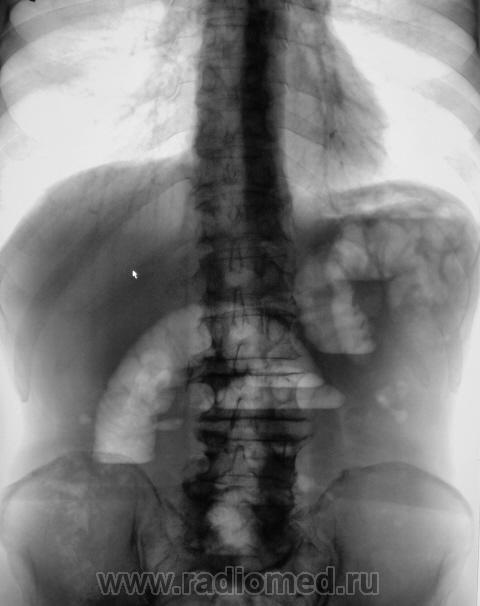

Промежуток между снимками - 5 минут. Направлен хирургом для рентгенографии брюшной полости. Диагноз при направлении - "Острый живот".

Признаки толсто-кишечной непроходимости, а почему интервал 5 минут?

Согласна. Видны арки или дуги. Намечается симптом пружины.

Признаки дистальной механической тонкокишечной непроходимости, свободный газ под левым куполом диафрагмы с уровнями жидкости в свободной брюшной полости - признак перфорации кишечника. Вероятно новообразование. Пациента необходимо срочно передавать хирургам.

Я не вижу свободного газа в брюшной полости.

Было подозрение на наличие "свободного" газа под левым куполом диафрагмы. Положили на левый бок, предполагая, что "свободный газ" переместится под правый купол. Вот, и объяснение наличия второго снимка.

Важный дифференциальный признак механической и паретической непроходимости  - стабильность картины на снимке через 5 минут при паретической непроходимости, и нестабильность (как в данном случае) при механической. Так что "Убивали двух зайцев".